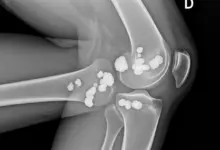

Na prática, a osteotomia ao redor do joelho é indicada com mais frequência para corrigir desalinhamentos, redistribuir carga articular e preservar a articulação em perfis selecionados, sobretudo quando ainda há espaço para adiar procedimentos mais agressivos.

A osteotomia do joelho entra no planejamento quando existe desalinhamento do membro, sobrecarga localizada e quadro compatível com preservação articular.

Em boa parte dos casos, o raciocínio cirúrgico busca mudar o eixo mecânico para reduzir a pressão sobre a área mais sofrida.